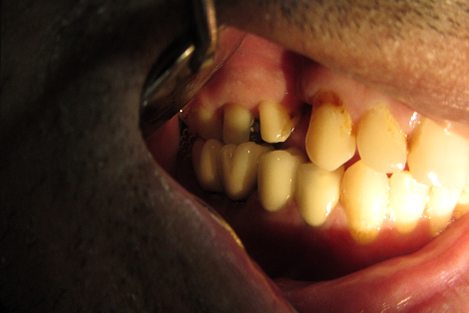

Post n Core